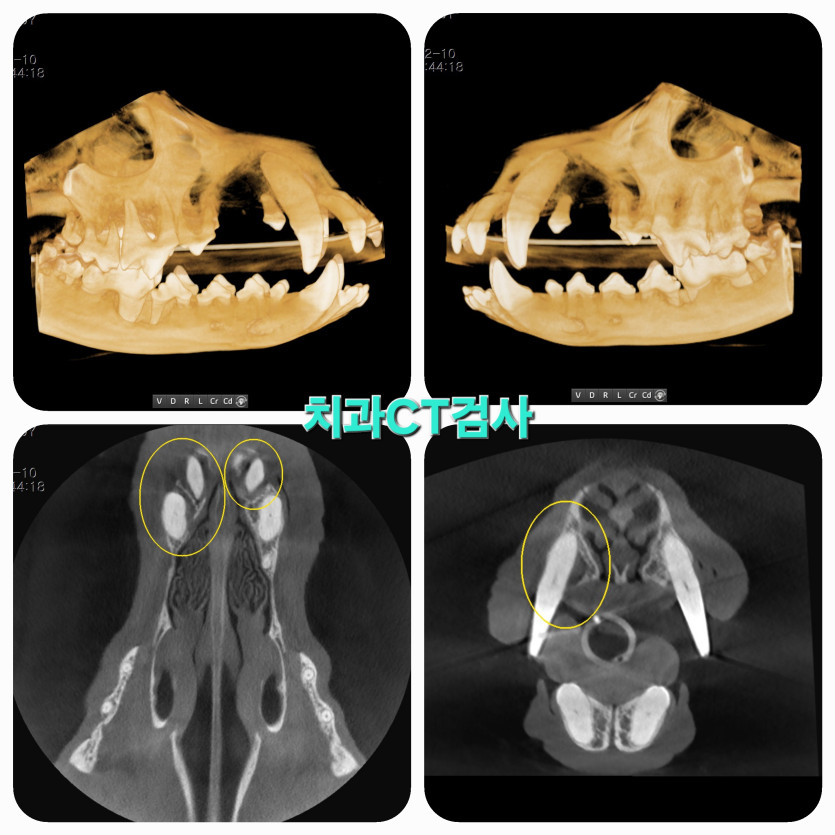

저희 강아지는 매일 양치를 시켜도 치아가 약해 나이가드니 치주염과 이가 썩어서

정확한 진단에 강아지를 진심으로 사랑하시는게 마음 깊이 와닿아서 믿고 맡길 수 있었어요.

의사선생님은 초코의 상태를 정확히 진단하시고 아이가 더 이상 아프지 않게 치료해줬어요.